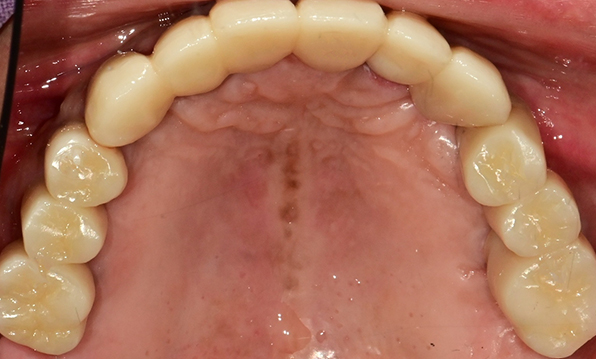

전체 임플란트

위 아래 치아가 정확하게 맞아야하는 고난이도 임플란트

임상 경험이 많은 숙련된 전문의의 섬세한 기술력이 중요합니다.

치료기간 : 2021.04.12~2021.09.15